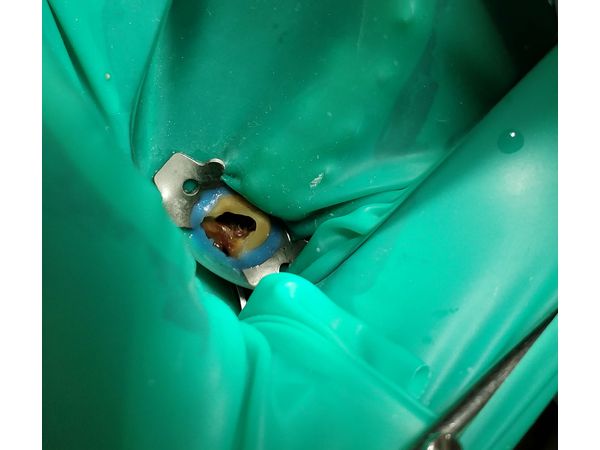

- Врач-ортопед отсепарировал (отделил) 17 зуб от соседних и снял постоянную ортопедическую конструкцию. Изоляция произведена системой коффердам (пластиной из латекста).

- После снятия пломбы — некрэктомия (удаление нежизнеспособных тканей), восстановление стенки для проведения эндодонтического лечения (лечения корневых каналов).

- Дезобтурация (удаление старой пломбы) корневых каналов, заполненных резорцин-формалиновым цементом.